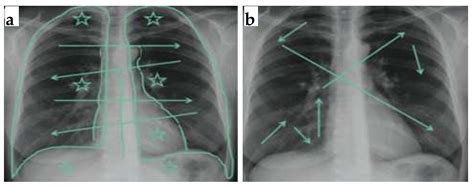

A lung nodule is medically defined as an opacity or a growth that measures less than 3 centimeters in diameter. If the growth is larger than 3 centimeters, it is typically classified as a lung mass, which requires a more urgent investigation. These nodules appear as rounded shadows on imaging scans and can be found in any part of the lungs. It is crucial to remember that finding a nodule does not automatically equate to a cancer diagnosis; in fact, the vast majority of lung nodules identified in clinical practice are found to be benign, meaning they are non-cancerous.

Radiologists use specific criteria to evaluate the risk profile of a nodule. By examining the shape, border, density, and growth rate, doctors can estimate the probability of malignancy. The following table summarizes how medical professionals categorize these features:

Feature Typically Benign (Low Risk) Typically Malignant (High Risk)

Border Smooth, sharp, or clearly defined Spiculated, irregular, or "fuzzy"

Calcification Central, popcorn, or dense Stippled or eccentric

Growth Rate Stable over years Rapid doubling in size

Density Solid, fat-containing Part-solid or ground-glass